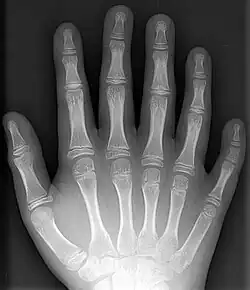

An X-ray of a hand with a supernumerary digit (polydactyly)

Supernumerary body parts are most commonly a congenital disorder involving the growth of an additional part of the body and a deviation from the body plan. Body parts may be easily visible or hidden away, such as internal organs.